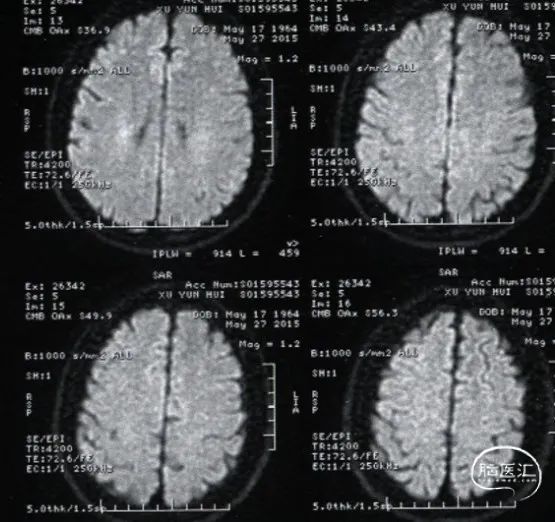

复查头颅MRI:无新发脑梗。

CTA提示前颅窝底异常扩张的血管。